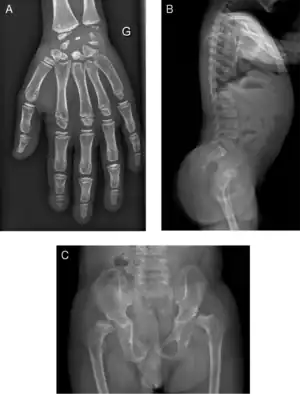

Radiograph of a WRS child presenting with dysplastic bone growth in various regions of the body. | |

Initially, patients with neonatal or early-childhood onset diabetes are possible candidates for having Wolcott–Rallison syndrome.[1] The other features include multiple epiphyseal dysplasia, osteopenia, intellectual disability, and hepatic and renal dysfunction.[1] Patients having features that suggest Wolcott–Rallison syndrome can be referred for genetics testing. The key way to test for this disease is through genetic testing for EIKF2AK3 mutations.[8] Molecular genetic analysis can be done for the patient and the parents to test for inherited or de novo mutations. It can also show whether the patient's parents are heterozygotes or homozygotes for the normal genotype.[4] X-rays can show bone age in relation to actual age. In typical WRS patients the bone age is a few years less than the chronological age.[4][5][9][10] Hypothyroidism is rare in WRS patients but can occur.[4]